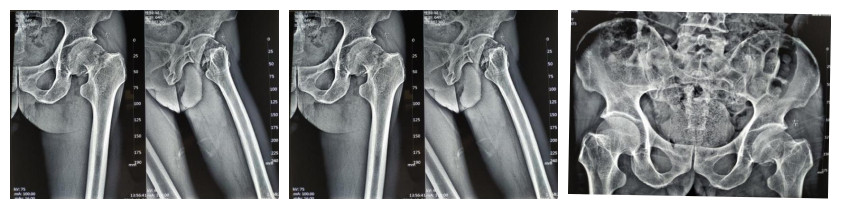

患者王某某,男性,64岁,因“摔倒致左髋疼痛、畸形伴活动受限1小时”于2018年12月1日急诊入院,查体:左下肢外旋畸形、短缩,活动明显受限,不能站立及行走,左髋部肿胀,皮肤稍红,局部触之皮温稍高,触压痛明显,稍活动引起疼痛加剧,可触及明显骨擦感,左下肢纵向叩击痛(+)。左膝部屈伸稍活动受限,左下肢肌力、肌张力正常,感觉正常,血运可。我院左髋关节CT骨三维重建:左股骨颈骨折。诊断:左股骨颈闭合性粉碎性骨折(头下型)。

术前左髋关节X线片:

考虑患者年迈六旬,其左股骨颈粉碎性骨折,断端嵌顿、移位,行螺钉固定术极易引起股骨头缺血坏死,且恢复周期长,手术风险高。骨科陈祥权主任医师、郑国钦科主任及骨科同道就这ー病历展开讨论,结合患者需求及预后,拟行“左髋全髋关节置换术”,并制定详细的手术方案及术后康复锻炼计划,排除相关手术禁忌征后,在全麻下手术顺利,达到预期效果。